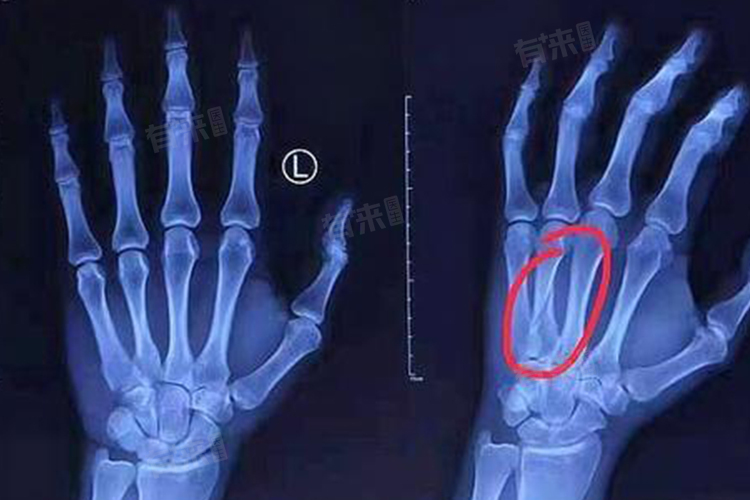

- 骨折指由于外力作用,导致骨骼完整性的全部或部分损害,包括完全骨折和不完全骨折。完全骨折是指骨骼完全断裂成两部分或更多部分,而不完全骨折则是指骨骼的完整性只是部分损害,如裂纹骨折。

- 骨裂通常是指轻度骨折,也就是不完全骨折的一种。骨裂时骨骼的完整性只是部分损害,如裂纹出现在骨头的一部分,但骨头没有完全断裂。骨裂可以看作是骨折的一个较轻的类型。